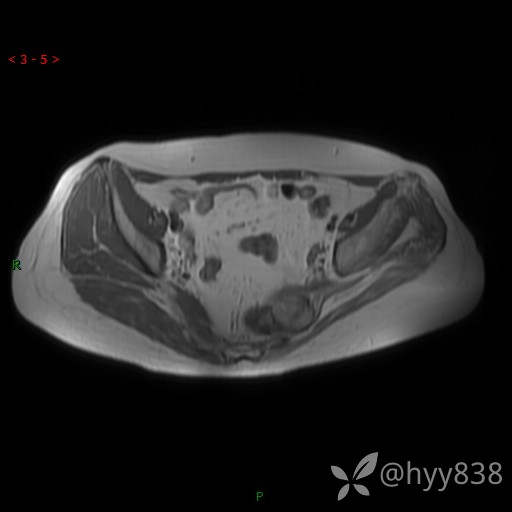

骨盆MRI平扫(T1WI+T2WI+DWI)(外院CT,不能上传)